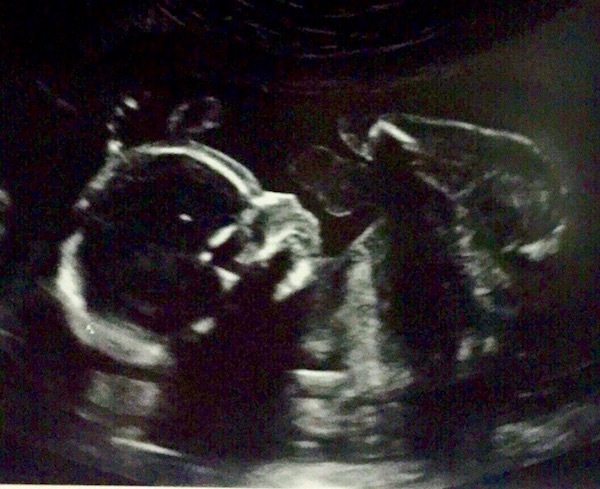

So far the most exciting moment of my pregnancy thus far has been seeing Madeline at our 20 week ultrasound! We even got to see her yawning and stretching in the womb! It was such an incredible experience! Sean and I left our appointment in awe of how God knits together a child in the womb, a beautiful masterpiece formed by His hand.